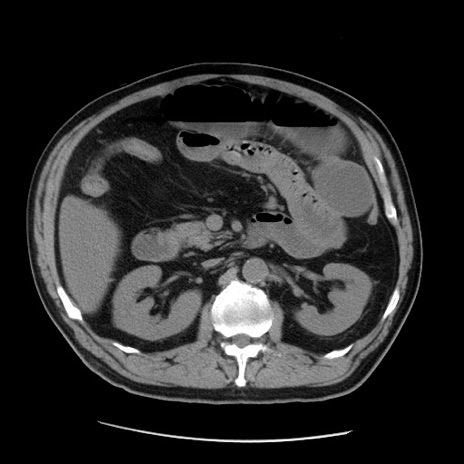

症例20(横断像)

【症例】 60歳代男性

【主訴】 腹部膨満、嘔吐

【現病歴】5日前頃より倦怠感を認め食事量減少し4日前の朝嘔吐、食事摂取困難となった。 3日前近医受診し点滴施行され整腸剤などを処方された。 当日他院を受診し、腹部膨満著明、炎症反応の上昇(CRP10.8、WBC11200)あり、紹介受診となる。

【身体所見】 意識JCS1 受け答えがはっきりしないBP 111/57mHg、 P 67bpm、、BT35.2°C、SpO2 97%(RA)、 腹部:膨隆、打診で鼓音あり、全体的に圧痛有り、腸蠕動音(-)、反跳痛ははっきりせず。

【データ】WBC 11400、CRP 14.20